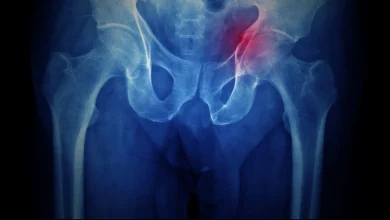

شکستگی لگن در دوران کرونا: ایران شاهد روندی غیرمنتظره در درمان بود

به گزارش پایگاه خبری علمی ریشامگ، با شیوع پاندمی کووید-۱۹ در سراسر جهان، سیستمهای مراقبتهای بهداشتی با چالشهای بیسابقهای روبرو…

هشدار برای بیماران مبتلا به شکستگی لگن با ترومای خفیف: خطر شکستگی مجدد و مرگ در سال اول

به گزارش پایگاه خبری علمی ریشامگ، مطالعه جدیدی که در مجله BMC Geriatrics منتشر شده نشان داد که افراد مبتلا…